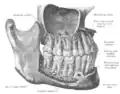

![]() Mandíbula humana. Face Medial (Superfície interna). Vista lateral | |

Sua forma é semelhante a uma ferradura horizontal com abertura posterior (corpo), de cujas extremidades livres saem dois prolongamentos (ramos).

Na parte posterior, há uma articulação sinovial, com os ossos temporais através do processo condilar, alongado ortogonalmente ao plano medial; esta articulação designa-se temporomandibular (ATM).

Cada lado contém, da extremidade anterior à posterior, oito alvéolos para a inserção dos dentes, respectivamente: dois alvéolos para o engaste dos incisivos; um alvéolo canino, bastante profundo; dois alvéolos pré-molares e dois ou três molares, dependendo da formação ou não do terceiro molar ou dente siso. Estes números referem-se à boca do homem, nos restantes grupos de mamíferos, os números variam, tendo evoluído de acordo com o tipo de alimentação.

Ainda sobre a anatomia humana da mandíbula humana nota-se a inserção de todos os músculos da mastigação, tendo como principais o masseter, o músculo temporal e os pterigóides, medial e lateral.

Estruturas

Fazem parte da mandíbula:

- Alvéolo dentário.

- Ângulo da mandíbula.

- Canal da mandíbula.

- Canal de Serres.

- Côndilo.

- Corpo da mandíbula.

- Forame da mandíbula.

- Forame mentual.

- Fóvea pterigóidea.

- Incisura da mandíbula.

- Língula da mandíbula.

- Linha milo-hióidea.

- Linha oblíqua.

- Processo coronóide.

- Protuberância mentual.

- Ramo da mandíbula.

- Sínfise da mandíbula.

- Sulco milo-hióideo.

- Trígono retromolar.

- Tubérculo geniano.

- Tuberosidade massetérica.

- Tuberosidade pterigóide.